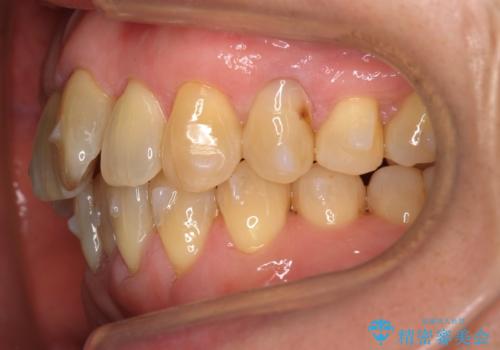

- 前歯のがたつきを主訴に来院。

右下の犬歯が歯ぐきが痩せて、歯肉退縮しておりそれを抜歯しました。

上の前歯はIPRを行なっています。

右下の犬歯の1本抜歯で最小限の抜歯で並べることができました。

奥歯も上下交互になるようにかみ合わせることができました。